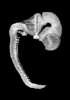

Carnegie Stage 18 (44 post-ovulatory days)

Most embryos at stage 18 are approximately 44 postovulatory days old and measure 13-17 mm in length. Distinguishing criteria for this stage include cervical and lumbar flexures, distinct notching in the hand plate, the first appearance of the elbow, eyelid folds may appear in more advanced specimens, and auricular hillocks begin to form distinct parts of the external ear.